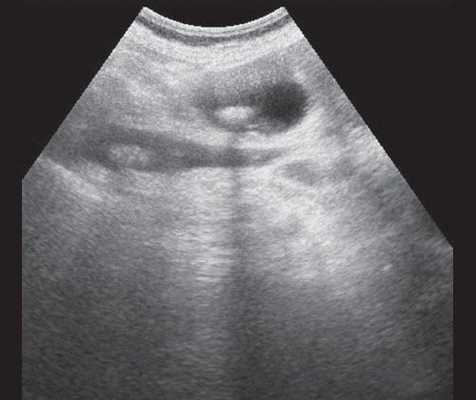

(Левый) При цветовой допплерографии на поперечном УЗ срезе печени наблюдается легкое расширение внутрипеченочных желчных протоков их диаметр немного превышает два миллиметра. Причиной легкой дилатации желчных протоков стала обтурация конкрементом (не показан).

(Правый) При цветовой допплерографии на поперечном УЗ срезе печени наблюдается небольшое расширение внутрипеченочных и внепеченочных протоков. У пациента был диагностирован стеноз ампулы в сочетании с холангитом, которые стали причиной дилатации желчных протоков.